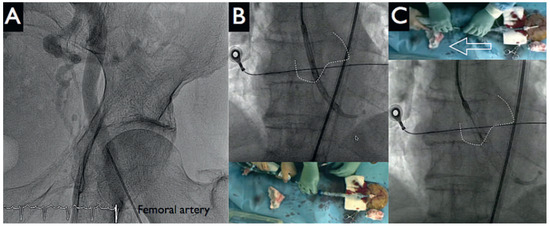

HeartMate PHP Axial Pump for High-Risk PCI

by Diego Arroyo, Serban Puricel, Mario Togni and Stéphane Cook

Cardiovasc. Med. 2016, 19(9), 241; https://doi.org/10.4414/cvm.2016.00430 - 21 Sep 2016

Percutaneous left ventricular assist devices (pVADs) can provide temporary circulatory support during high-risk percutaneous coronary interventions (PCIs). We describe the first case in Switzerland of high-risk PCI with a new pVAD, the HeartMate PHP axial pump (St Jude Medical). Full article